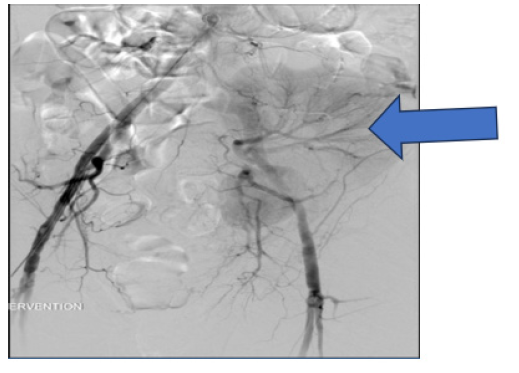

Figure 1: axial CT image: heterogenous mass just inferior to the transplant kidney measuring an estimated 7 cm x 5.cm (add arrow).

He subsequently underwent aortoiliac angiogram by interventional radiology at our institution which revealed a large pseudoaneurysm 5.2 cmx4.3cm arising from the lower pole renal transplanted artery. The PSA selectively and successfully coiled (Figures 3,4). Post procedure, he did well and discharge home without any y adverse effects from the endovascular procedure and remains off dialysis.